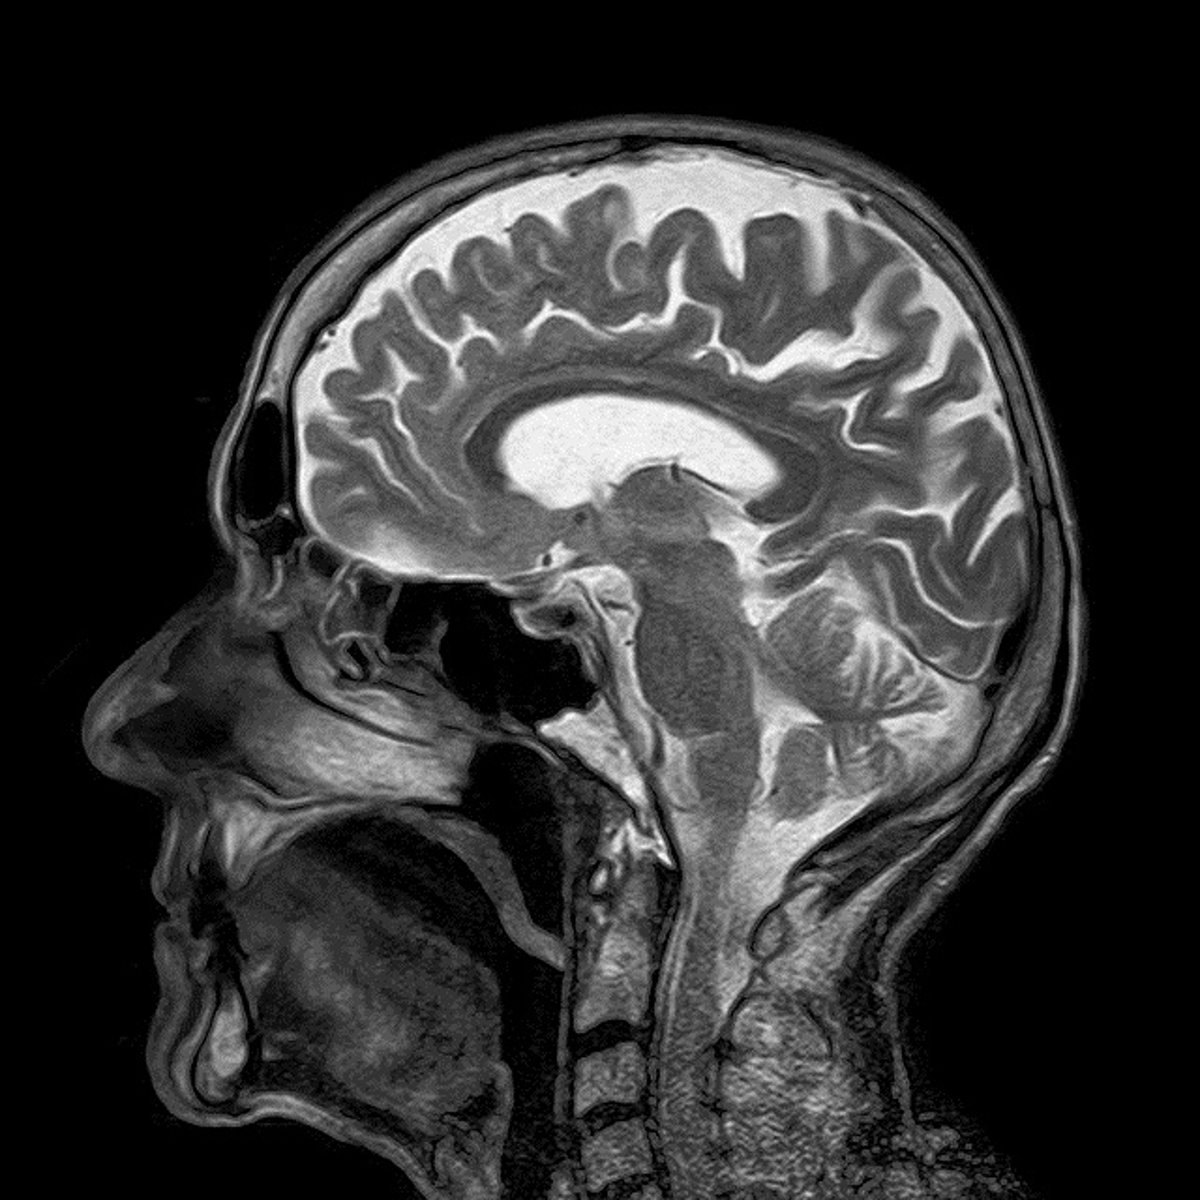

Investigadores de la Universitat Pompeu Fabra (UPF) han descubierto que una sustancia derivada del cannabis y sin efectos adictivos, el cannabidiol, logra disminuir el consumo de cocaína gracias a que facilita la proliferación de les neuronas (neurogénesis) en una región del cerebro implicada en la formación de memorias, el hipocampo, y resta protagonismo a los recuerdos asociados a la droga.

El estudio, publicado en 'Addiction Biology', ha estudiado en ratones el mecanismo por el que esta sustancia logra disminuir el consumo de la cocaína, y han descubierto que lo hace gracias a que dificulta la formación de memorias que se asocian a la droga con su efecto positivo, impidiendo que se creen recuerdos "aberrantes".

La adicción a las drogas puede considerarse como un desorden del aprendizaje y la memoria, ya que al consumirla, se crean memorias asociadas a la experiencia y su contexto, que se vuelven inalterables y aberrantes, lo que impide que se puedan olvidar las experiencias positivas asociadas a la droga.